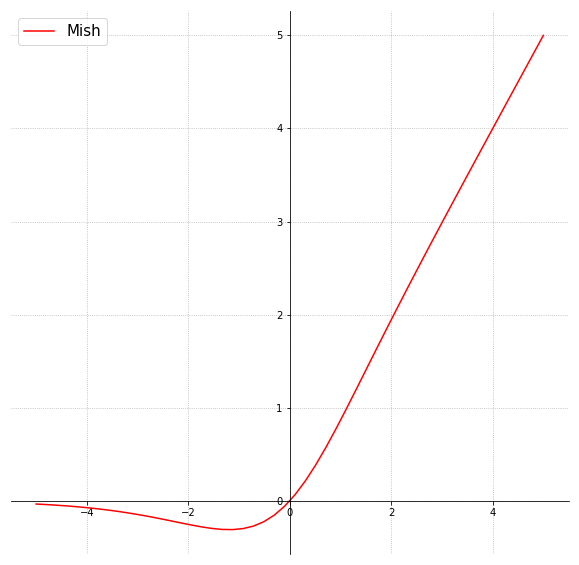

Fig. 1 shows the general flow of the proposed approach for polyp detection in colonoscopy images. As shown in Fig. 2, the proposed deep CNN consists of 16 convolutional layers, two fully connected layers, and a softmax layer. To lessen computational complexity and improve hierarchical image features, maxpooling is used for the first 15 convolutional layers. For better image feature extraction, different sizes of convolution kernels are employed, with a stride of 2. In the proposed model, we have implemented Mish [21], which is a self-regularized smooth non-monotonic activation function, in the first 15 convolutional layers. This implementation was done after extensive trials to find the best matching position of the activation function. As observed in Fig. 3, Mish is an unbounded above result in avoiding saturation due to capping. This may normally lead to slow training, i.e., near-zero gradients. A better gradient flow and smooth propagation of information across deeper layers are achieved by the infinite order of continuity and a small allowance of negative values, in comparison to a strictly bounded rectified linear unit (ReLU) as an activation function. MISH can be expressed mathematically as:

In the last layers, ReLU is used as an activation function to reduce the likelihood of gradient vanishing and achieve the sparsity. Flattening is done by two fully connected layers to yield a single continuous linear vector followed by softmax or the regression layer to generate the required output. The approach of using Mish and ReLU as an activation function results in smooth propagation of information across deeper layers. MISH helps to avoid capping, and ReLU prevents the gradient from vanishing.